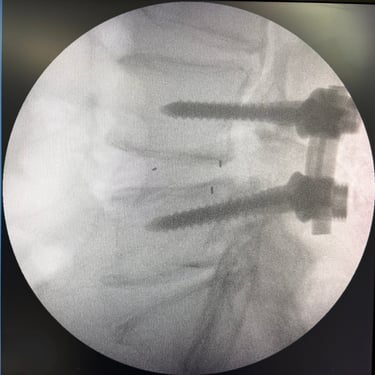

Estabilización con Fijación Transpedicular (FTP) y Fusión Intersomática Transforaminal (TLIF)

La listesis L4–L5 asociada a estenosis lumbar severa se caracteriza por el deslizamiento vertebral y el estrechamiento del canal espinal, generando dolor lumbar, claudicación neurogénica y compromiso radicular. Cuando el tratamiento conservador no logra un control adecuado de los síntomas, la fijación transpedicular (FTP) asociada a la fusión intersomática transforaminal (TLIF) constituye una alternativa quirúrgica eficaz. Este procedimiento permite descomprimir las estructuras nerviosas, restaurar la alineación vertebral y proporcionar una estabilización sólida del segmento afectado, favoreciendo una recuperación funcional segura y una mejor calidad de vida.